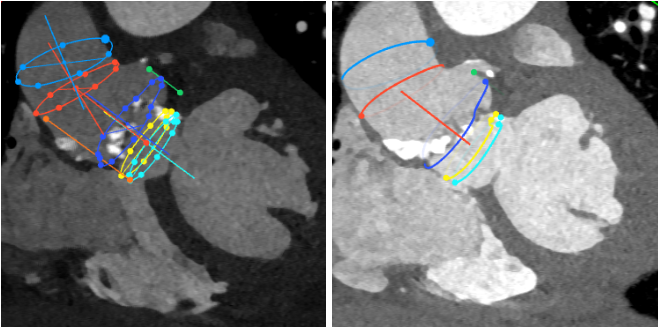

CT分析结果:

图示:瓣环、左室流出道、主动脉窦、升主动脉、窦管结合及瓣上结构部大小。

由于患者的主动脉根部扭曲程度很大,猪尾导管无法置于无冠窦底,钟炜教授在释放时通过精准控制输送系统和适时造影,最终完美完成了瓣膜的释放。

主动脉根部扭曲程度大

猪尾很难到达主动脉根部,释放难度大